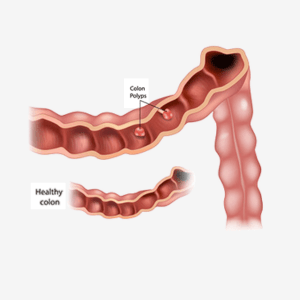

Colon polyps

Familial adenomatous polyposis